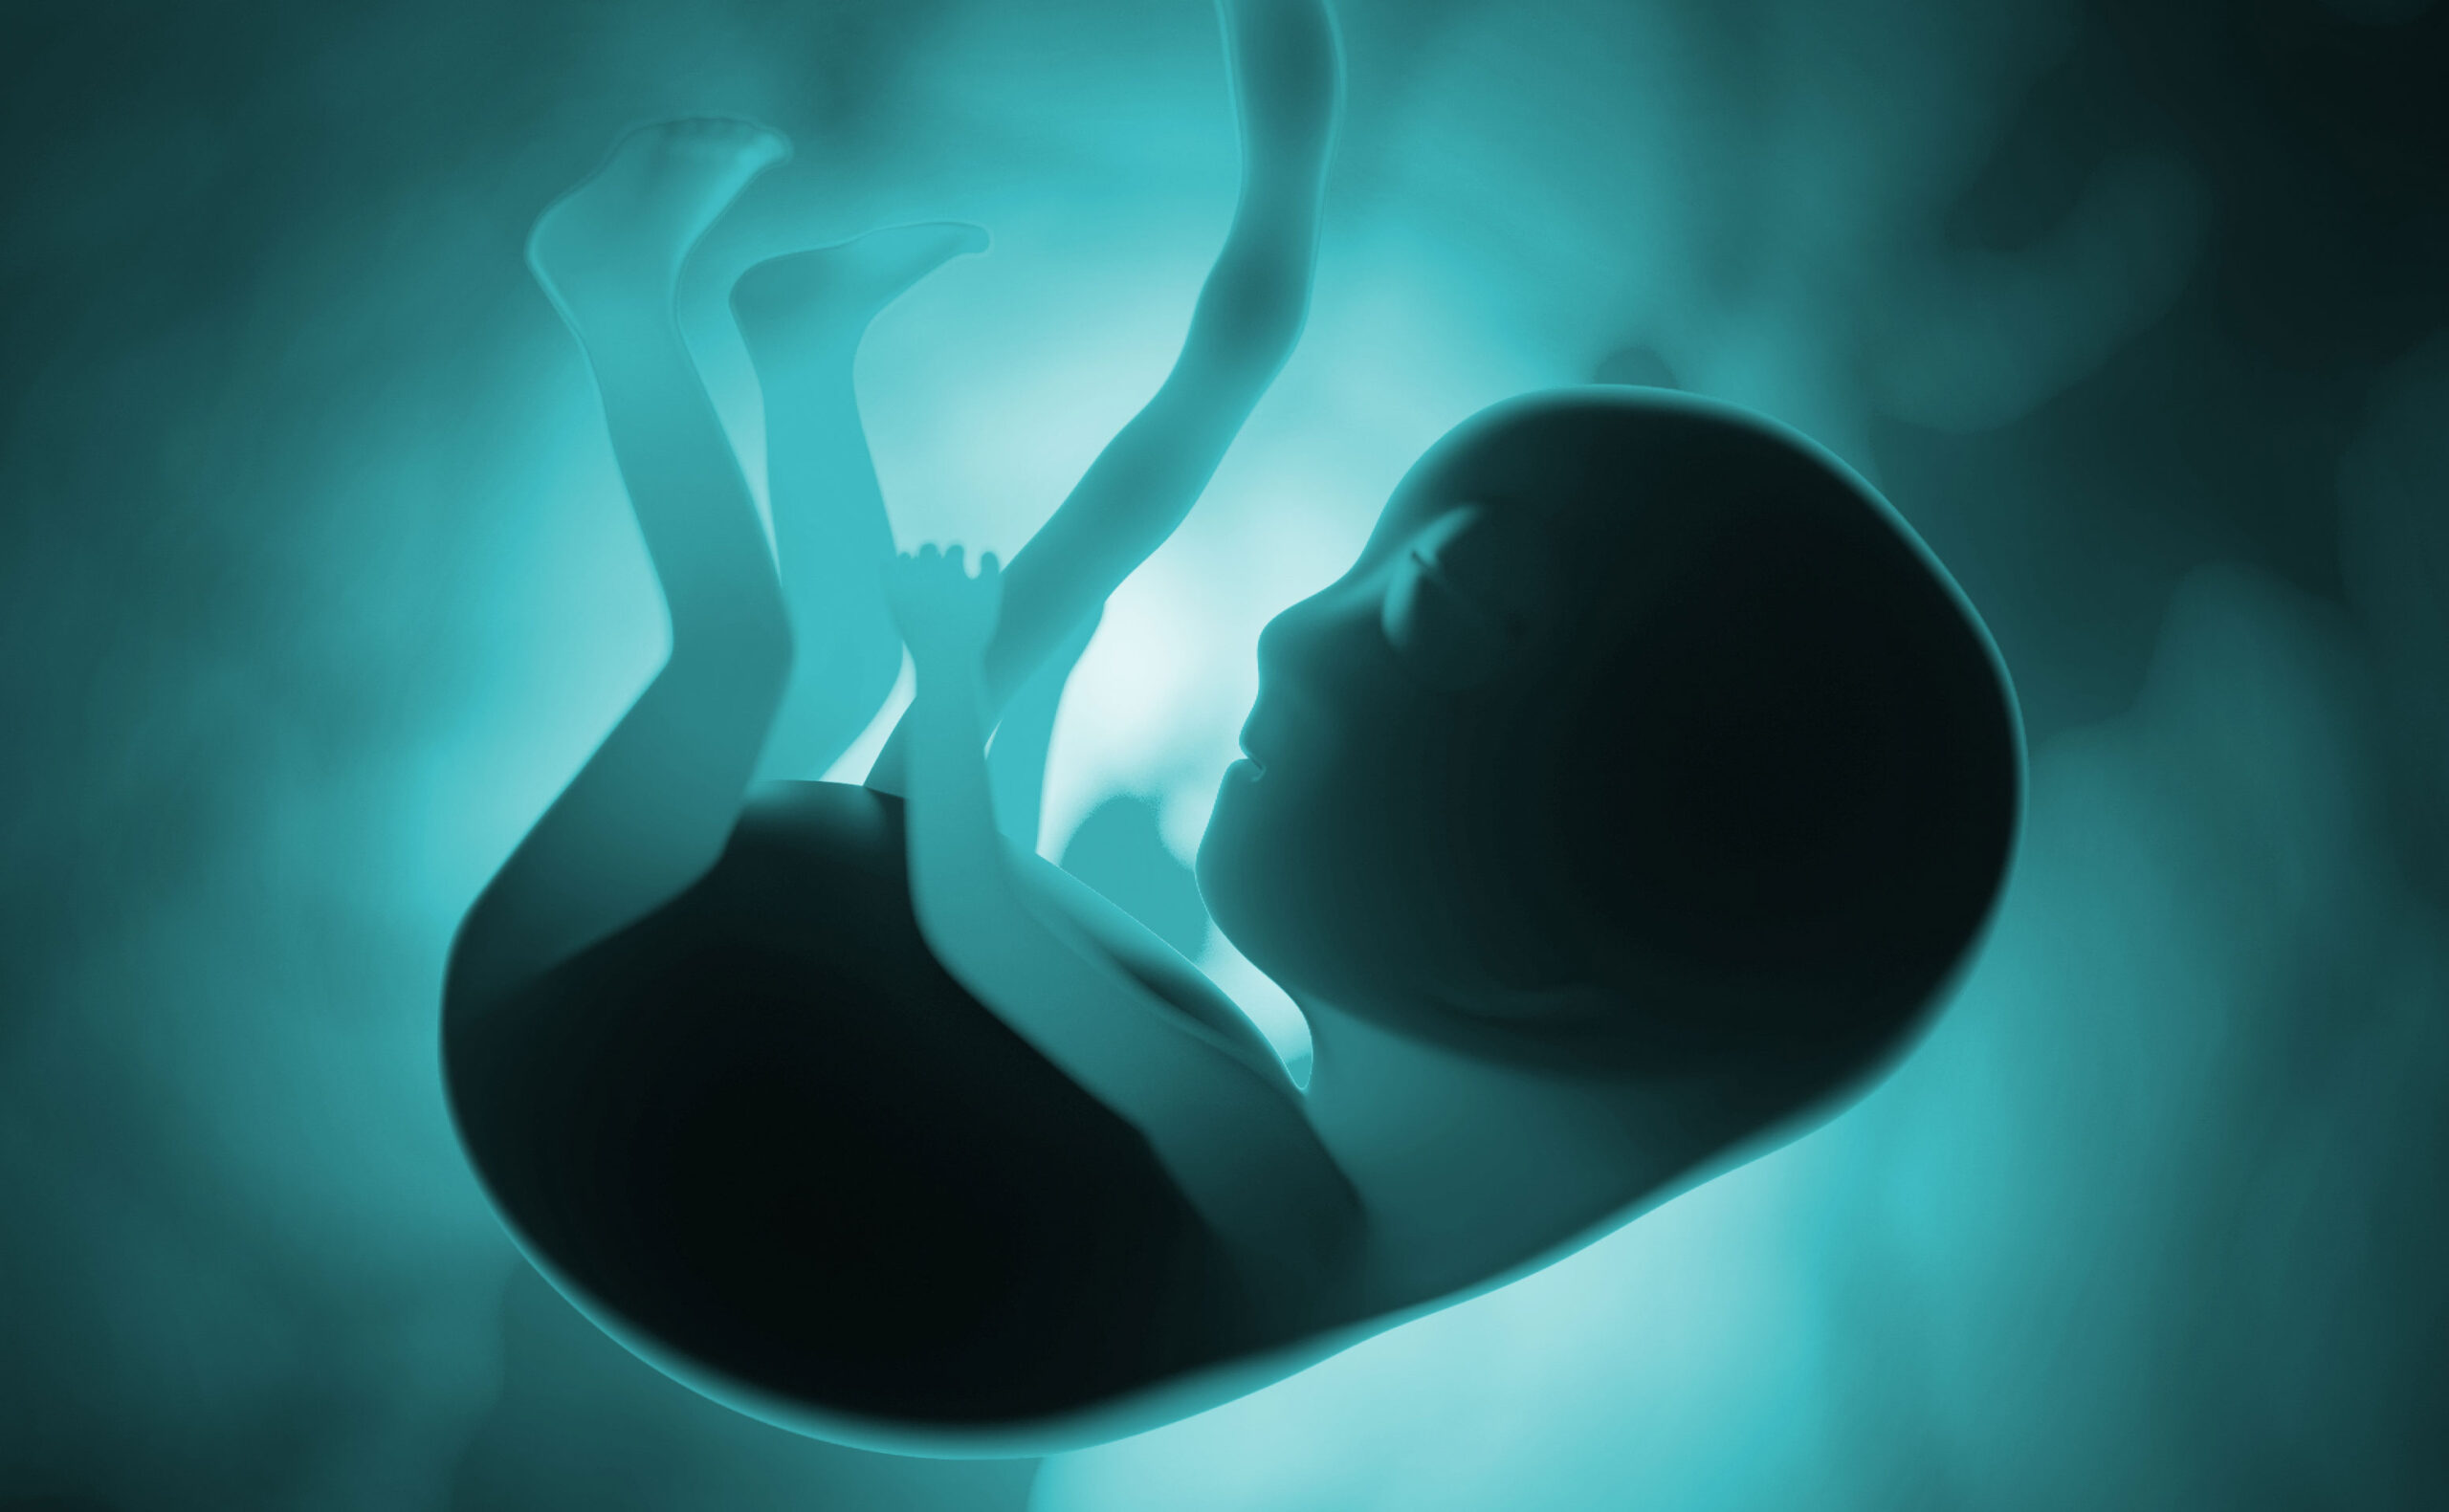

Этапы развития ребенка в утробе: фотографии и ультразвуковые снимки

Раздел: Лаборатория идей